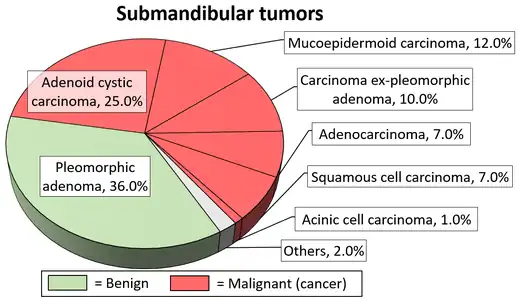

Diagrams by Mikael Häggström - ↑ Ghom AG; Ghom SA (1 July 2014). Textbook of Oral Medicine. JP Medical Ltd. p. 606. ISBN 978-93-5152-303-1.